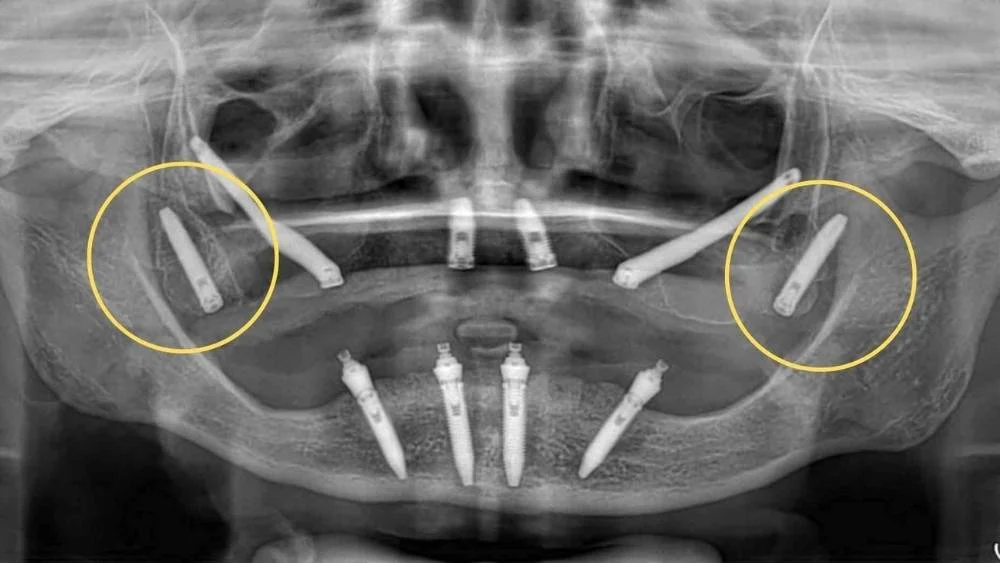

- A differenza degli impianti tradizionali, che vengono inseriti verticalmente nell’osso alveolare, gli impianti pterigoidei attraversano il seno mascellare (in alcuni casi lo sfiorano soltanto) e raggiungono la lamina del processo pterigoideo dell’osso sfenoide.

- Il posizionamento richiede una pianificazione chirurgica accurata, spesso con l’ausilio di TAC 3D e software di chirurgia guidata per identificare con precisione il punto di ingresso e l’angolazione corretta dell’inserimento, che solitamente è compresa tra i 30° e i 45°.

- Generalmente, si inserisce un impianto pterigoideo per lato, in combinazione con altri impianti anteriori per garantire il supporto di una protesi fissa completa. Questo schema consente di eliminare l’uso di cantilever (prolungamenti posteriori delle protesi) che potrebbero comprometterne la stabilità.

- Gli impianti zigomatici si ancorano nell’osso zigomatico, situato nella regione dello zigomo. Questo osso è estremamente denso e non è soggetto a riassorbimento osseo, il che lo rende ideale per il fissaggio implantare.

- Gli impianti pterigoidei sono inseriti nella zona della tuberosità mascellare, dietro i molari superiori, e si estendono fino al processo pterigoideo dello sfenoide, una struttura ossea molto dura e stabile.

- Gli impianti zigomatici sono i più lunghi, con lunghezze che vanno dai 30 ai 55 mm, proprio perché devono raggiungere lo zigomo partendo dalla cresta alveolare.

- Gli impianti pterigoidei hanno lunghezze comprese tra 15 e 25 mm, e sono comunque più lunghi dei tradizionali impianti endossei.